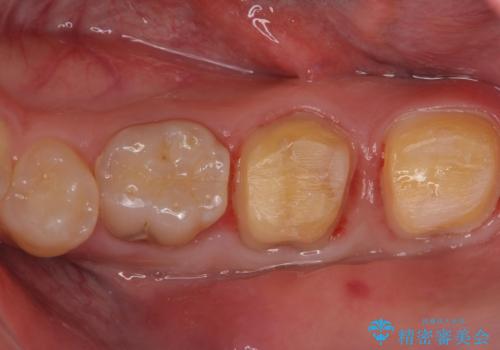

- 口の中を予算の範囲内でできるだけきれいにしたいとのことで来院された患者様です。

矯正治療と虫歯治療を組み合わせてご提案しましたが、ご予算との兼ね合いで虫歯治療のみを行うこととなりました。

奥歯は十分な歯の高さがなかったため、クラウンをかぶせる前に歯周外科治療で歯の高さを出しています。

歯科に通うようになってから磨き残しの状態も改善されていきました。